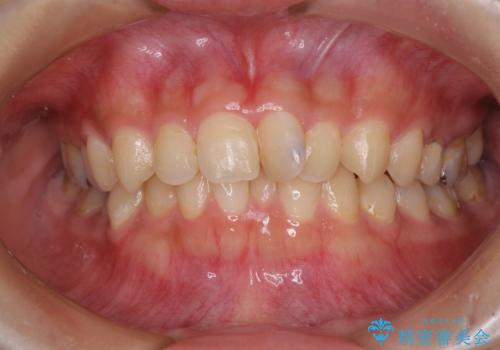

2級ディープバイト 遠心移動を伴うマウスピース矯正